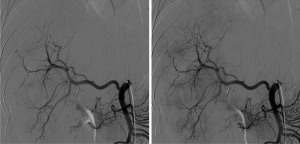

Angiographic lesion vascular grade assessment

Visual vascular grading of the lesions was performed using images obtained during diagnostic angiography. For each patient, two board-certified interventional radiologists blinded to the treatment regimen reviewed the digital subtraction angiograms. Angiographic tumor vascularity was categorized into 4 grades for each patient. We conducted our visual rating inspired by rating systems used in a study focusing on recurrent glioblastoma multiforme and anaplastic astrocytomas (10), another study utilizing digital subtraction angiography (DSA) for visual rating in gliomas (11), and research on the vascularization of liver metastases (12). The angiographic tumor vascularity of each patient was classified as follows: grade 1, avascular tumors; grade 2, mild tumor flushing; grade 3, tumor flushing with an arterial network; and grade 4, abnormal vascularization and arteriovenous shunting (Figures 1-4). Compared with the reference study (12), the lesions of patients with grade 1 and 2 tumors in our study showed similar or less contrast enhancement than the normal parenchyma, aligning with the hypovascular class in the reference. In contrast, the lesions of patients with grade 3 and 4 tumors, which exhibited a higher contrast than the surrounding hepatic parenchyma, corresponded to the hypervascular class in the reference study.